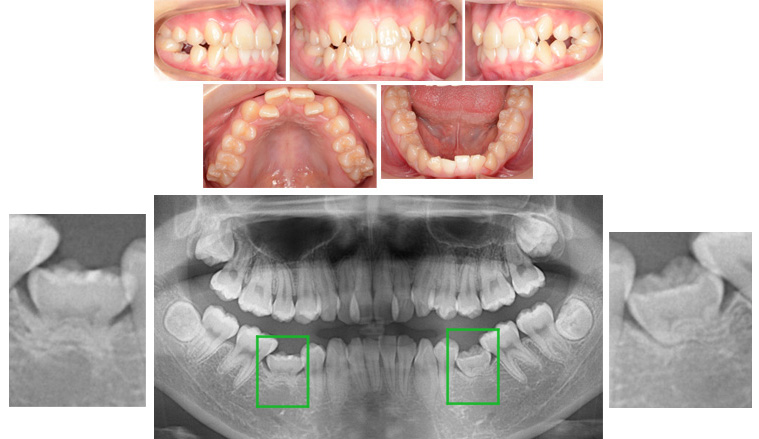

来院時の写真

気になっている点(主訴): 下顎第二乳臼歯の晩期残存

下顎の第二小臼歯の先天欠如はよくあります。この患者様もそうです。こういった場合は第二乳臼歯(緑枠)の晩期残存が見られます。通常は第二乳臼歯が脱落すると第二小臼歯と生えかわります。しかし、その第二小臼歯がありませんでした。このままにしておけばインプラントあるいは入れ歯、ブリッジなどの処置が必要になります。そこで矯正治療をおこないました。

上顎に叢生がありました。上顎側切歯が内側に入り込んでいました。下顎は第二小臼歯が先天欠如していました。第二乳臼歯が晩期残存しています。その第二乳臼歯は低位乳歯と言われる状態でした。第二乳臼歯は骨と癒着して動けない状態です。高さも低いです。これは乳歯が骨に癒着したためにその部分の骨が成長できなかった。また第二小臼歯が欠如しているために骨が上方に成長できなかった事も考えられます。

抜歯部位 : 上顎両側第一小臼歯、下顎第二乳臼歯